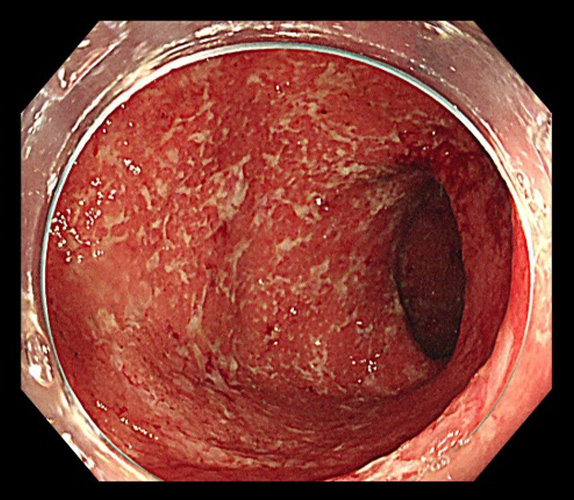

潰瘍性大腸炎

潰瘍性大腸炎は大腸粘膜に炎症や潰瘍が生じる原因不明の慢性疾患で、国から難病指定をされている病気の1つです。

自己免疫異常が関与するとされていて、発症のピークは20歳代〜30歳代ですが、若年者から高齢者まで幅広い年齢層で発症します。

症状として、血便や下痢、腹痛が特徴的で、炎症が強い場合は頻繁に血便が見られ、貧血や体重減少を伴うことがあります。

薬物療法で炎症をコントロールすることが治療の中心となりますが、重症例などでは外科手術が必要になることもあります。